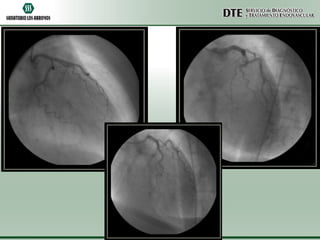

Cinecoronariografía

•Arteria descendente anterior de fino calibre y aspecto

hipoplásico.

•Arteria circunfleja y coronaria derecha sin lesiones

angiográficamente significativas.

•Acinesia de punta y segmentos apicales de pared anterior

e inferior.

•Moderado deterioro de la función sistólica ventricular

izquierda.